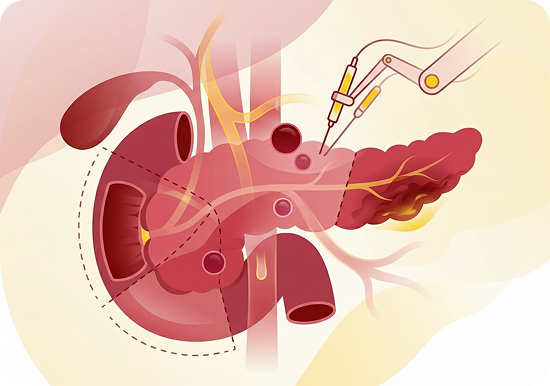

Pancreatic Surgery

- Whipple procedure (Pancreaticoduodenectomy)

- Distal and total pancreatectomy

- Minimally invasive and robotic-assisted pancreatic surgery

- Surgical management of pancreatic cysts and neuroendocrine tumour

- Vascular resections in pancreatic cancer surgery

- Surgical drainage of pancreatic pseudocysts

- Necrosectomy for infected pancreatic necrosis

- Surgery for chronic pancreatitis